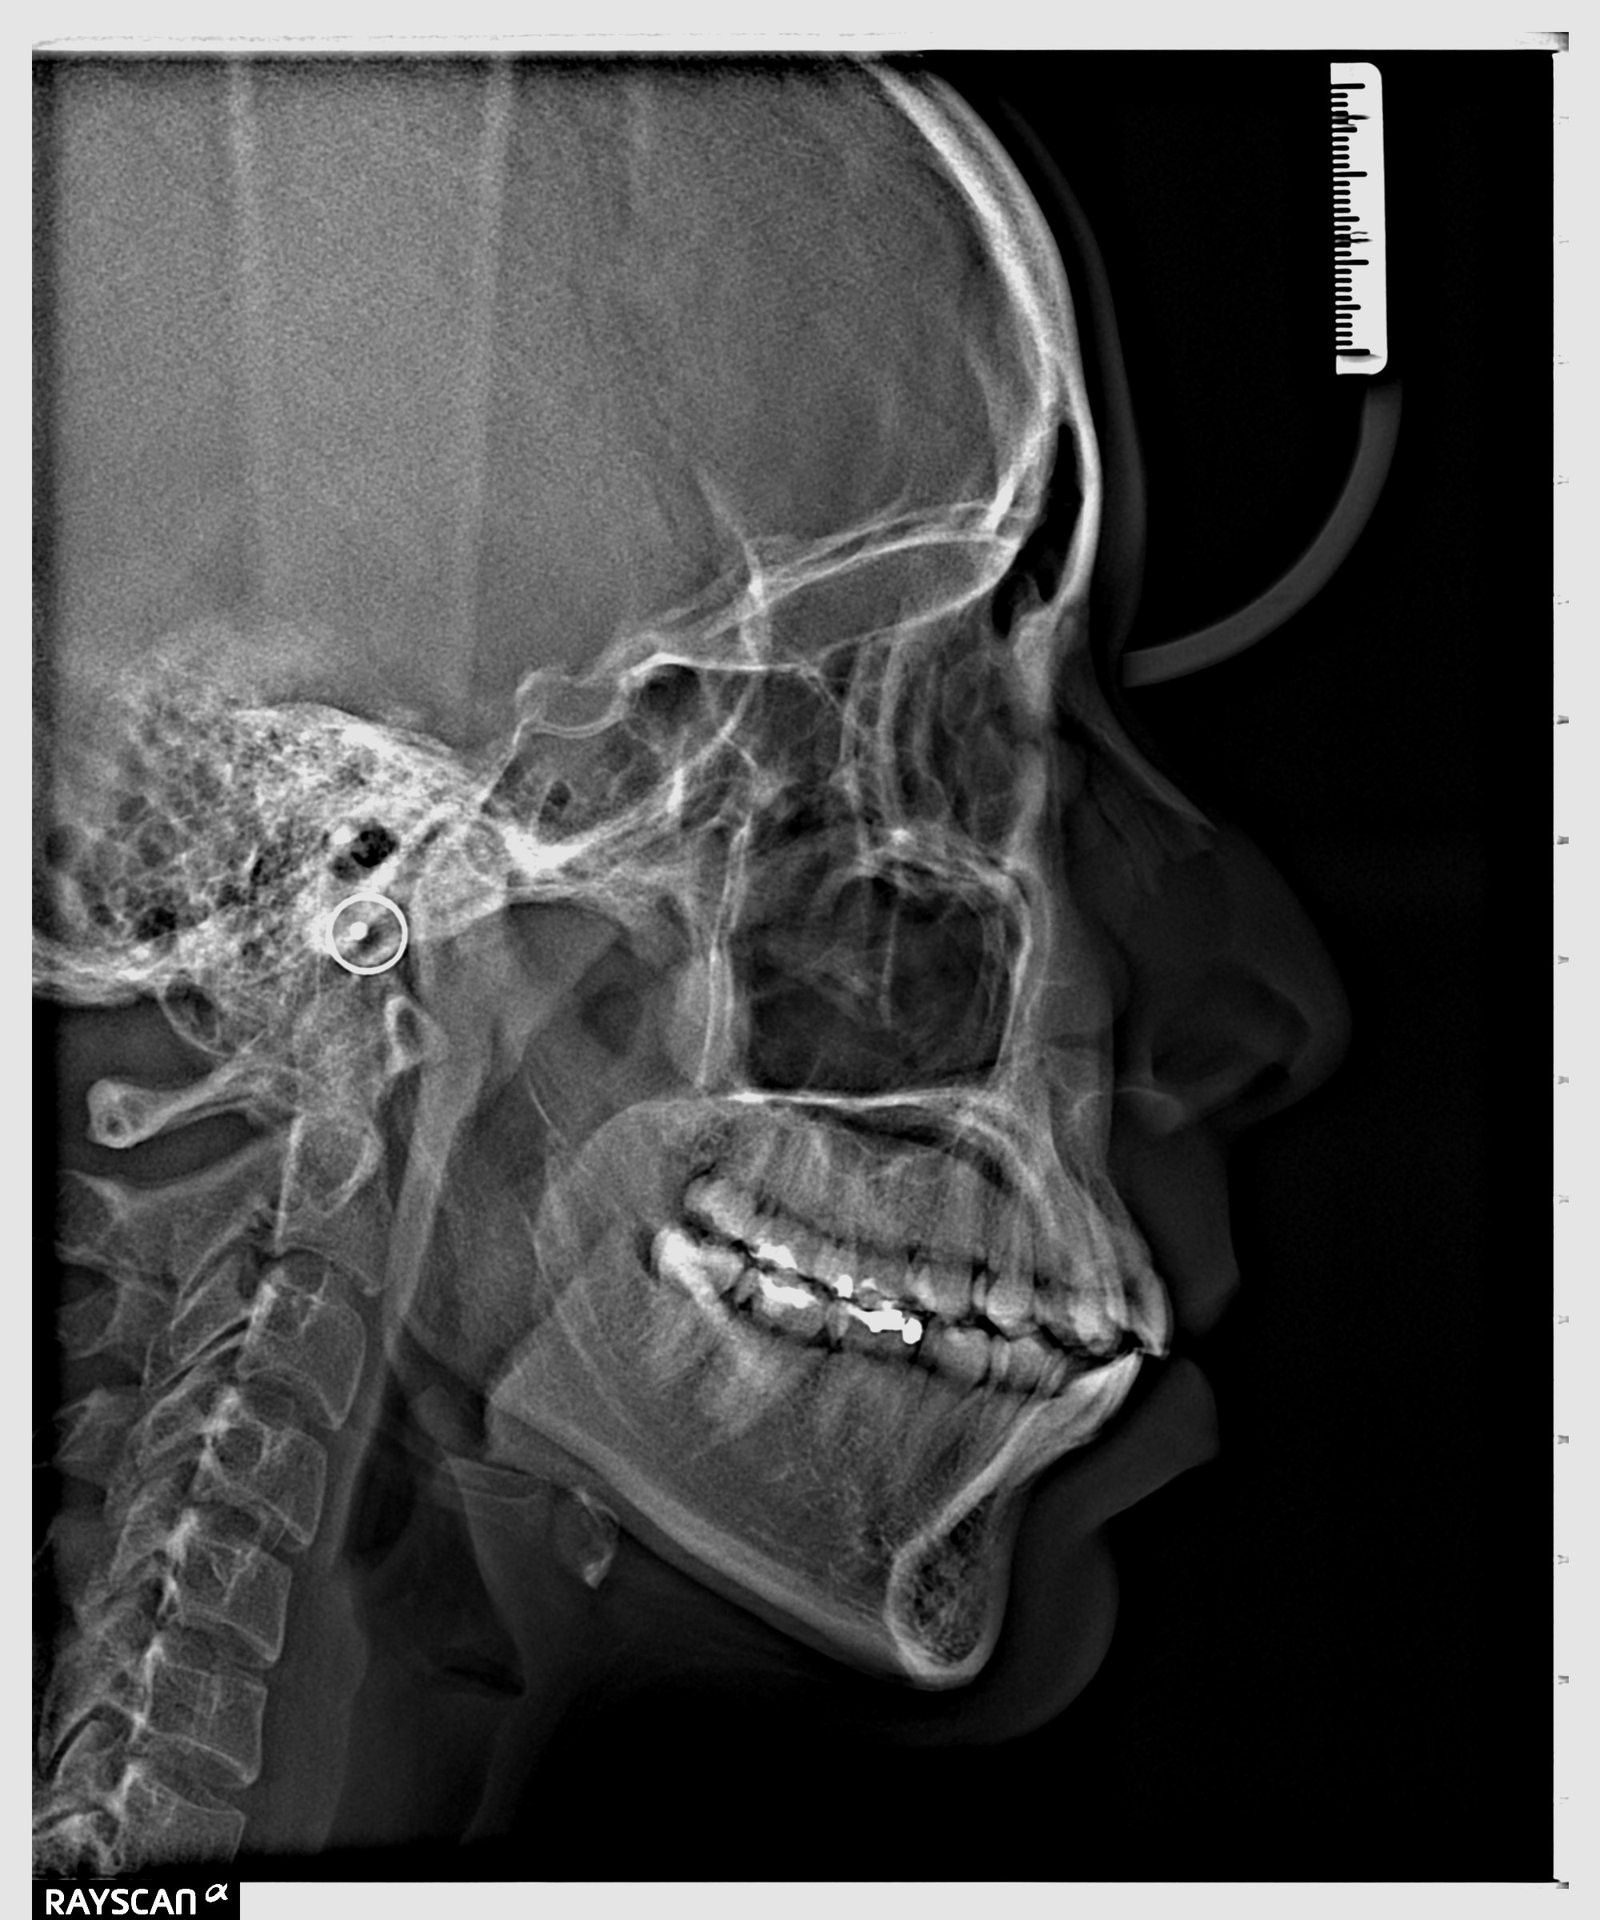

Toma de estudios radiográficos en placa radiográfica digital o impresión en disco compacto de:

- Ortopantomografías (panorámicas), cefalometrías (lateral de cráneo), articulaciones temporomandibulares con técnica de boca abierta y boca cerrada, senos paranasales, cráneos y carpal (de mano) para determinar edad ósea.

- Estudios ortodónticos completos con modelos de yeso, fotografías intra y extra oral, trazado cefalométricos con impresión de diagnóstica y pacas de rayos x panorámica y lateral de cráneo.

- Estudios ortodónticos intermedios con placas, panorámica, lateral de cráneo, fotografías intra y extra orales.

Radiografías panorámicas

Nuestro equipo permite la toma de este tipo de radiografías, todo lo

necesario para que pueda seguir adelante con su diagnóstico y tratamiento.

Este examen proporciona información de la

anatomía de los maxilares, superior e inferior a menor radiación.